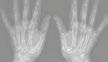

2.6.4 Radionuklidové metody (Daniela Chroustová) 35